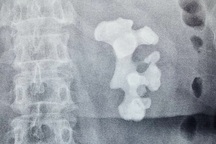

Viên sỏi san hô được các bác sĩ phẫu thuật, lấy ra khỏi thận trái của bệnh nhân, có kích thước 12x6cm (Ảnh: Bệnh viện cung cấp).

Qua thăm khám, các bác sĩ chẩn đoán ông T. có sỏi san hô phức tạp ở thận trái, kích thước lớn và được chỉ định mổ mở lấy sỏi thận. Sau gần 2 giờ tiến hành ca phẫu thuật, các bác sĩ đã lấy ra viên sỏi san hô với kích thước 12x6cm.